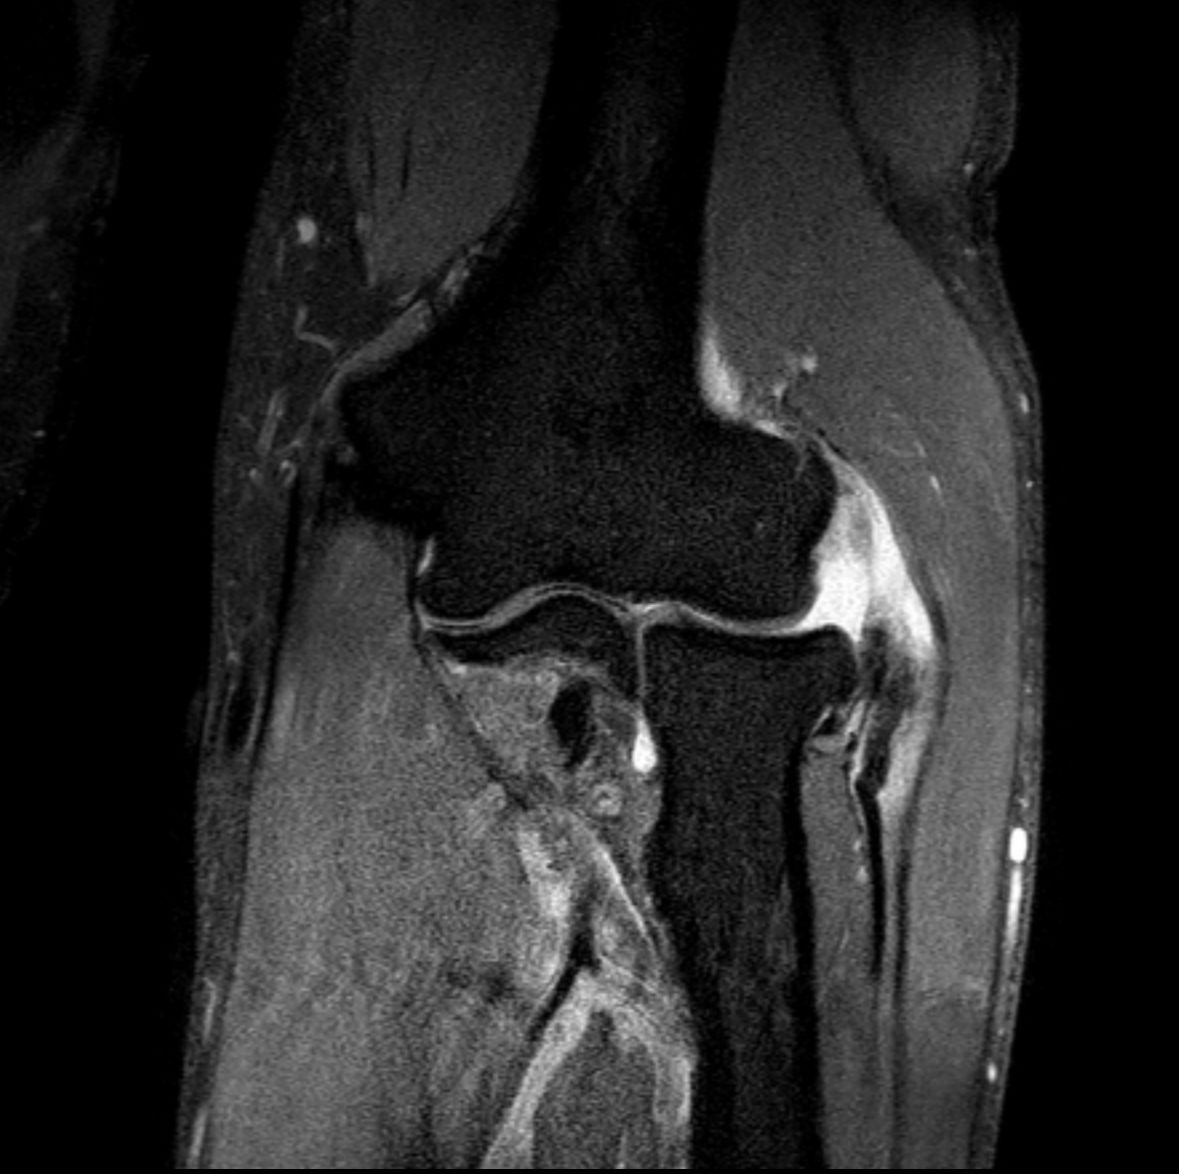

Steve tried 2 rounds of cortisone shots for elbow pain that originally gave him temporary relief-but also weakened the tissue. As the shots wore off the pain came back stronger. He was diagnosed with two partially torn tendons in his elbow, and his training came to a grinding halt. The gains started slipping. The mental fatigue was real. He was staring down a future that didn’t align with the commitment he’d made to himself.